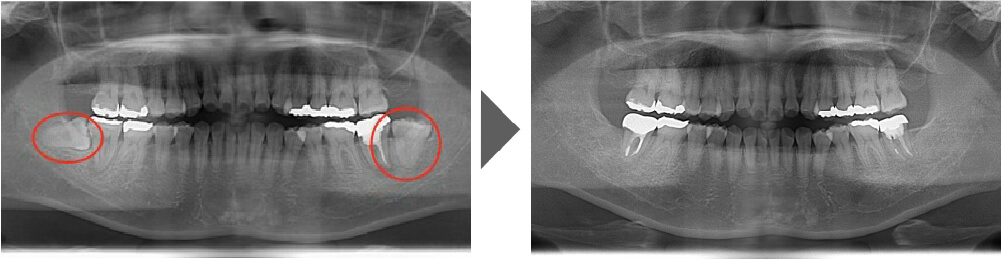

抜歯症例③

ご覧いただいた通り、生えている向きが真横に近い状態で、 通常は時間を要する抜歯です。

【抜歯所要予約時間】

15分

(麻酔の時間があるので処置自体はもっと短いです)